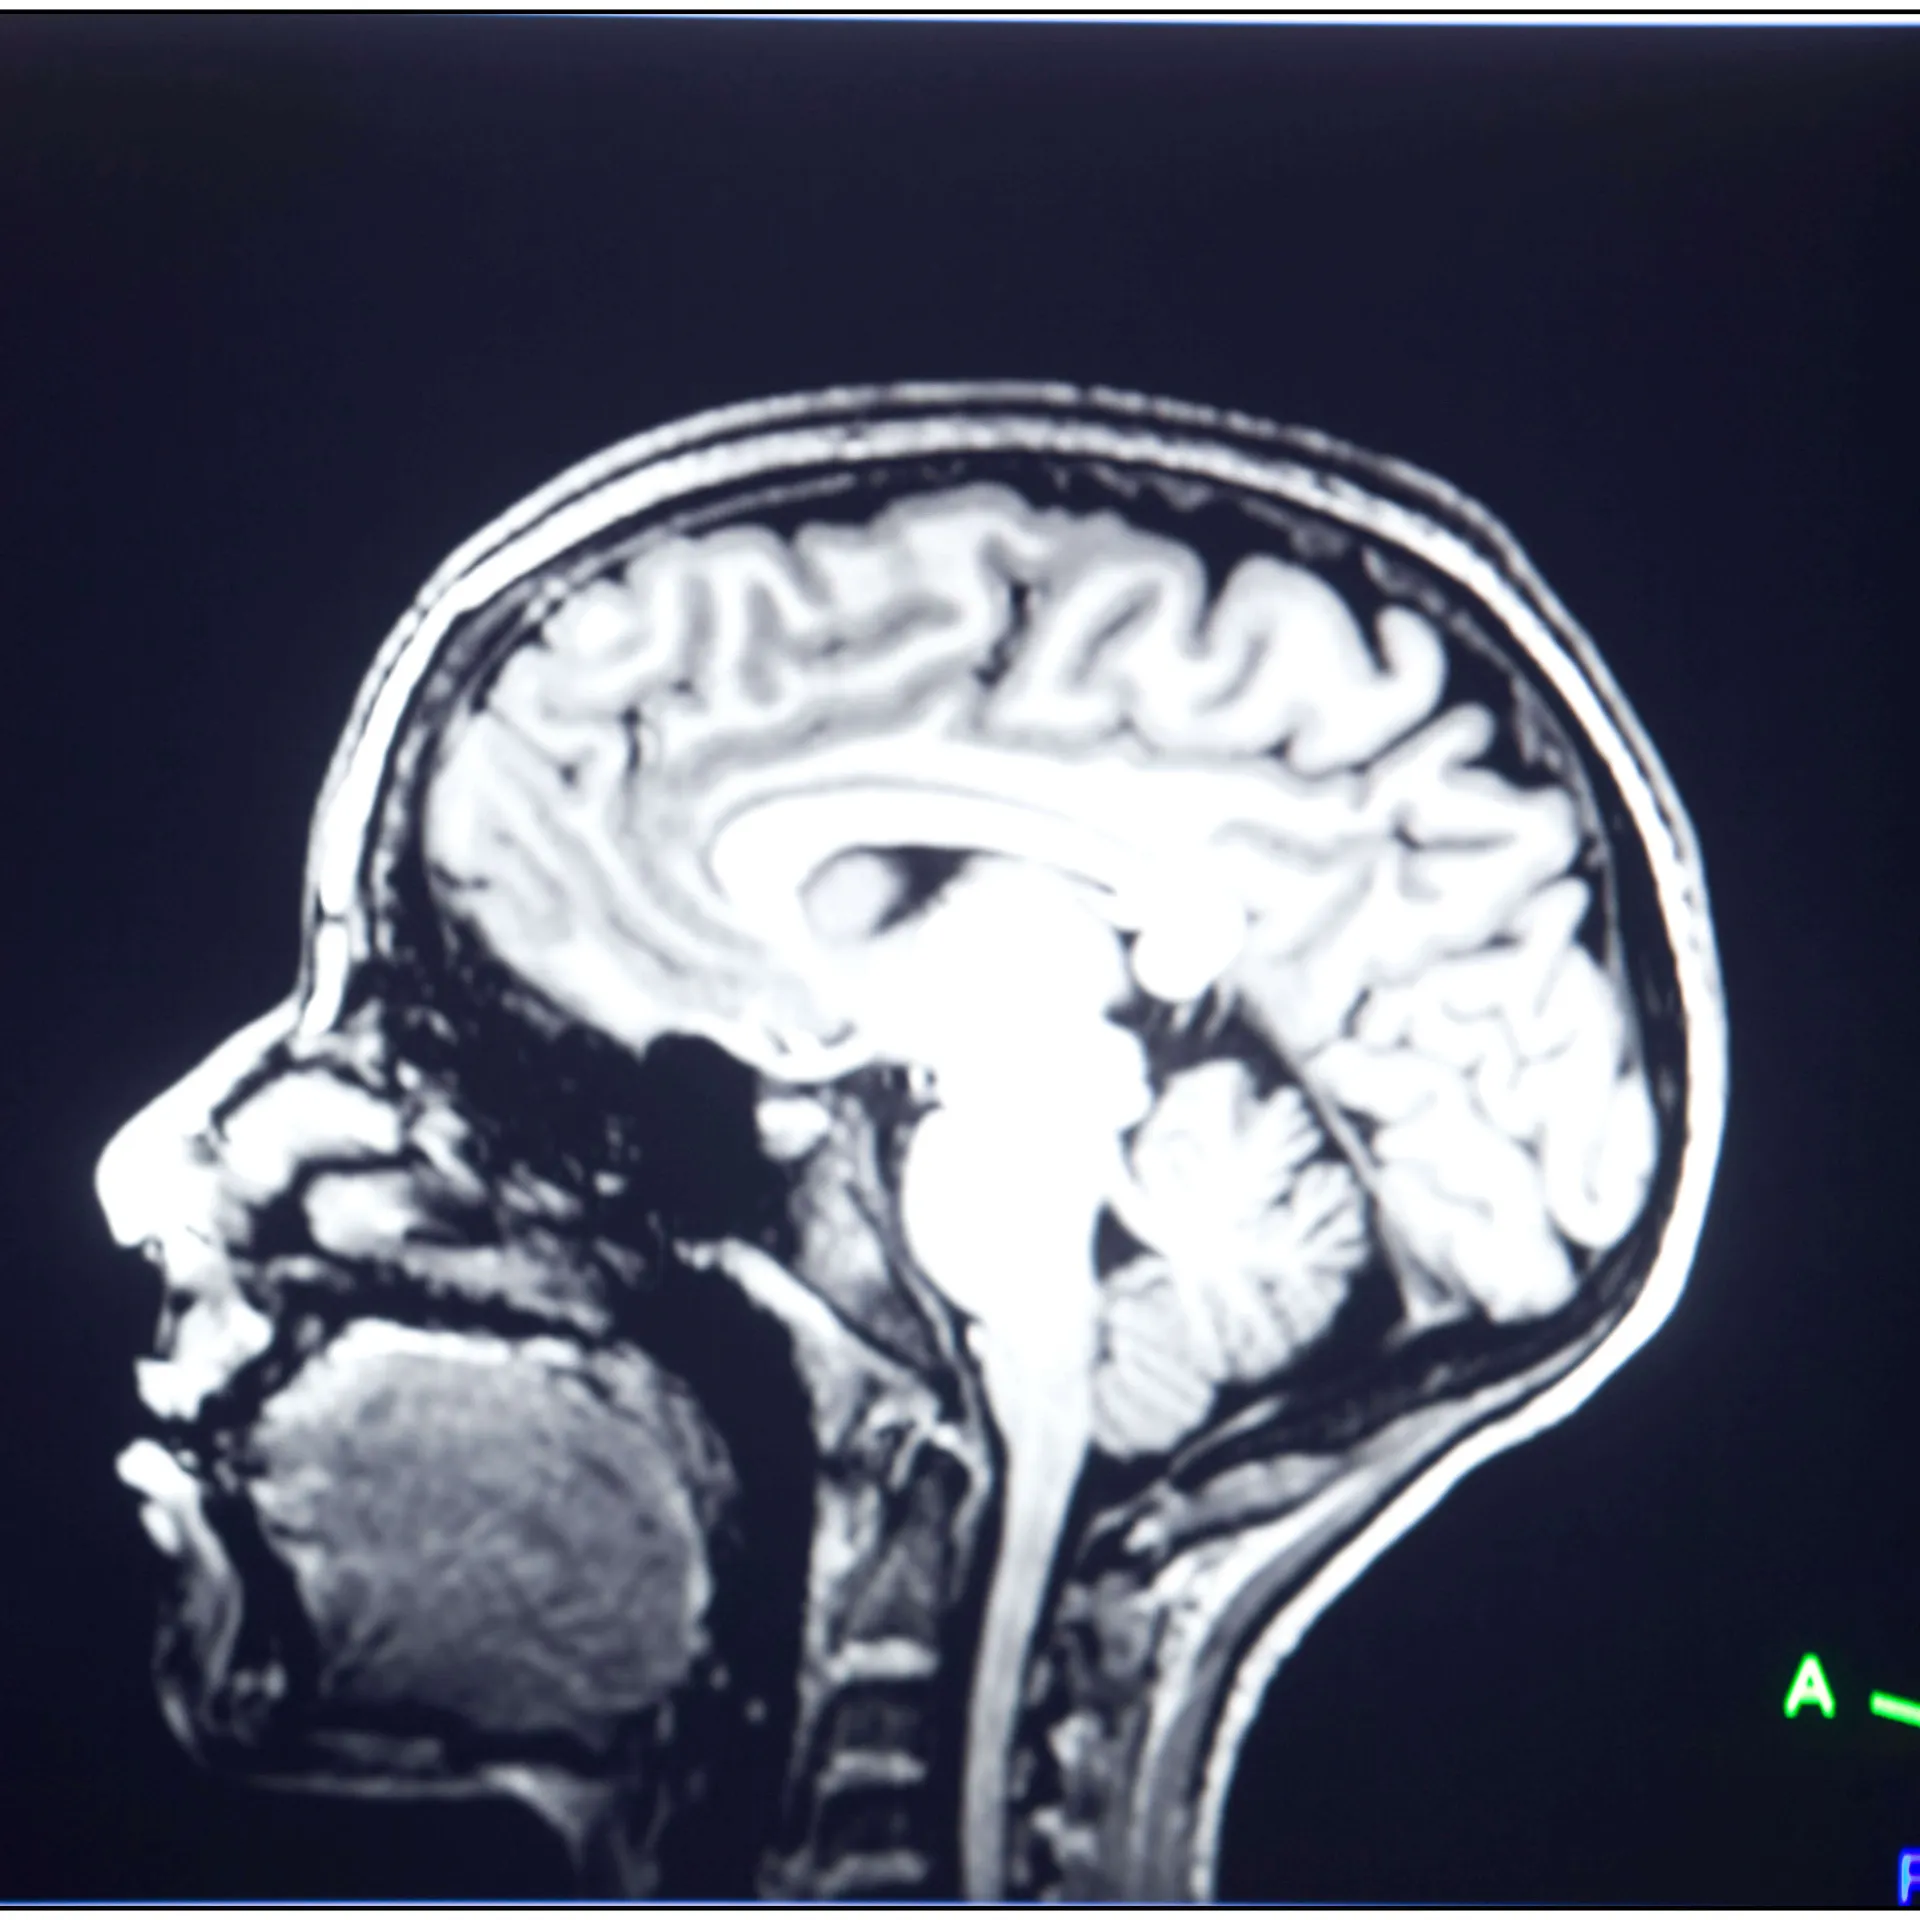

The University of Vermont Larner College of Medicine’s Division of Neurosurgery, Vermont's sole tertiary care center, offers comprehensive surgical management for brain, spinal cord, and peripheral nervous system disorders. Since 1948, we have focused on translating innovative research into enhanced patient care.